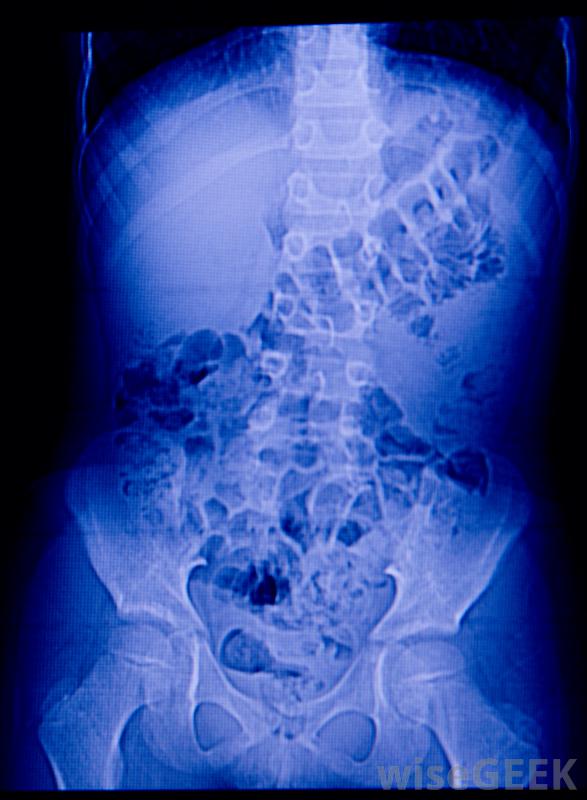

腎臟感染是一種急性疾病,通常是由細菌進入尿道并遷移到一個或兩個腎臟引起的。醫生把這種情況稱為腎盂腎炎,感染的嚴重程度可以是輕微的、幾乎不明顯的,甚至可能危及生命。如果一個人在小便時有灼熱感和頻繁劇烈的下背部疼痛,應立即到醫生那里接受腎臟感染的篩查。當疾病早期被發現時,它通常可以通過一個療程的抗生素治愈。X光可以幫助檢查腎臟感染引起的組織損傷一個人可以通過多種途徑感染尿道。不良的衛生習慣會導致糞便細菌進入尿道,尤其是女性。性傳播疾病、未消毒的婦科工具、生殖器急性損傷,自身免疫性疾病也會導致尿道和腎臟感染。很少情況下,腎結石或其他尿路阻塞會刺激腎臟內壁,增加細菌感染的風險腎臟感染可能來自腎結石或其他泌尿系阻塞。腎臟感染的癥狀可能不同,根據疾病的進展和涉及的細菌類型大多數病例會導致泌尿系統問題,如灼熱感和頻繁的沖動。偶爾,尿液中可能會有血。感染惡化時,患者可能會出現發燒、惡心和嘔吐。一些人的腹部、腹股溝或腰背劇痛。未經治療,腎臟感染可導致器官組織的永久性疤痕,最終導致腎功能衰竭。尿檢通常用于幫助診斷腎臟感染初級保健醫生通常可以通過評估患者的癥狀和收集血液和尿液樣本進行實驗室分析來診斷腎臟感染。如果醫生不確定根本原因,他或她可能會將病人轉介給腎臟科醫生作進一步的診斷測試。專科醫生可以檢視化驗結果,以識別特定的細菌,并進行x光檢查,以檢查組織損傷。在作出診斷后,醫生可以決定最佳的治療方案隨著腎臟感染的進展,可能會導致發燒、惡心,只有輕微癥狀的感染通常用口服抗生素治療。除了開藥外,醫生可以解釋良好衛生習慣的重要性,并建議定期檢查,以幫助預防未來的尿路問題抗生素治療通常可在兩周內有效地根除感染。腎臟感染者可接受靜脈輸液出現嚴重癥狀的患者可能需要住院,并接受靜脈輸液和藥物治療,以防止腎功能衰竭。如果可能發生腎功能衰竭,醫生可能會決定進行緊急外科手術。通過立即治療和幾個月的隨訪,大多數患者能夠在沒有永久性健康問題的情況下康復。在早期階段,可以使用抗生素治療腎臟感染。